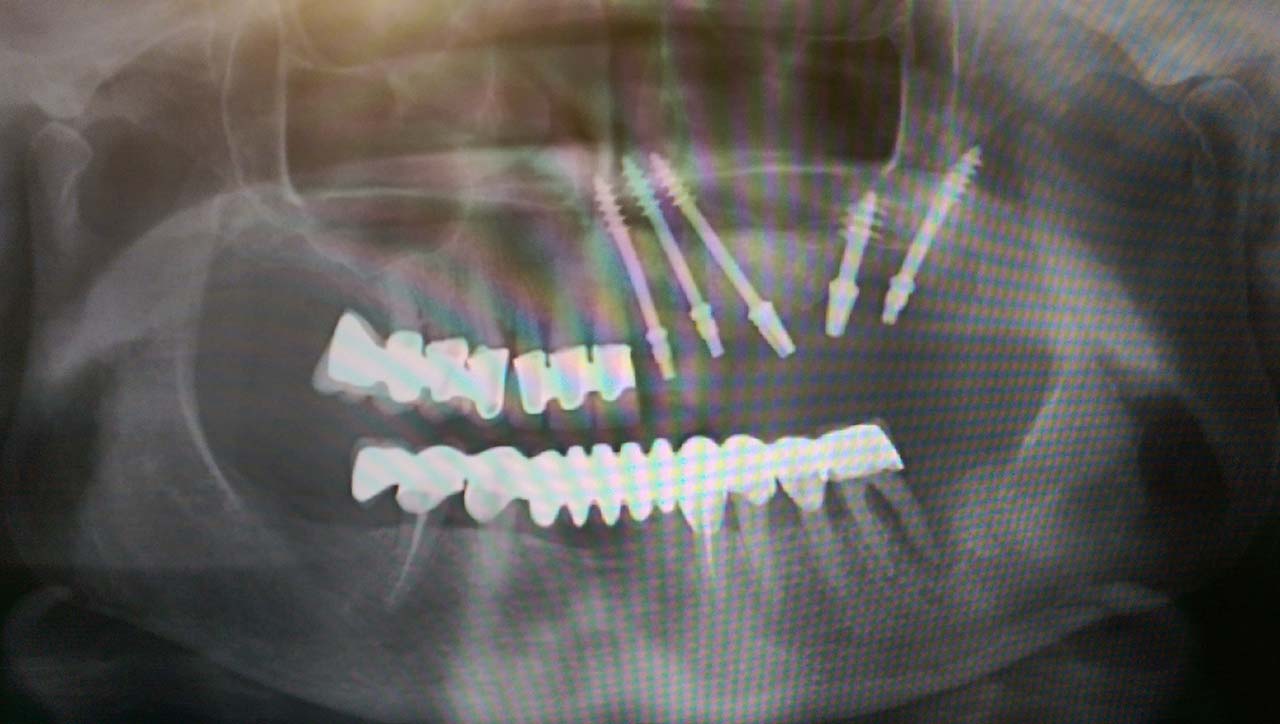

Teljes alsó,felső állcsont helyreállítása azonnal

terhelhető implantátumokkal és porcelán hidakkal.